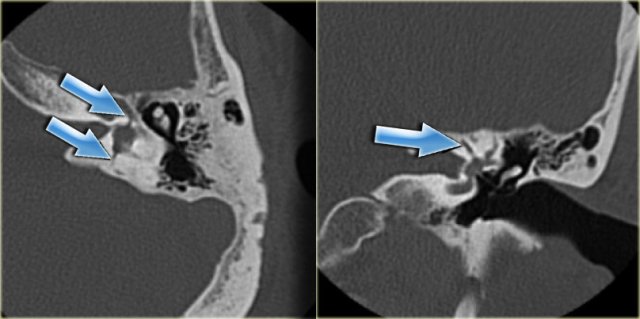

On the left axial and coronal images of a 50-year old male.

Incidental finding of a jugular bulb diverticulum (arrows).